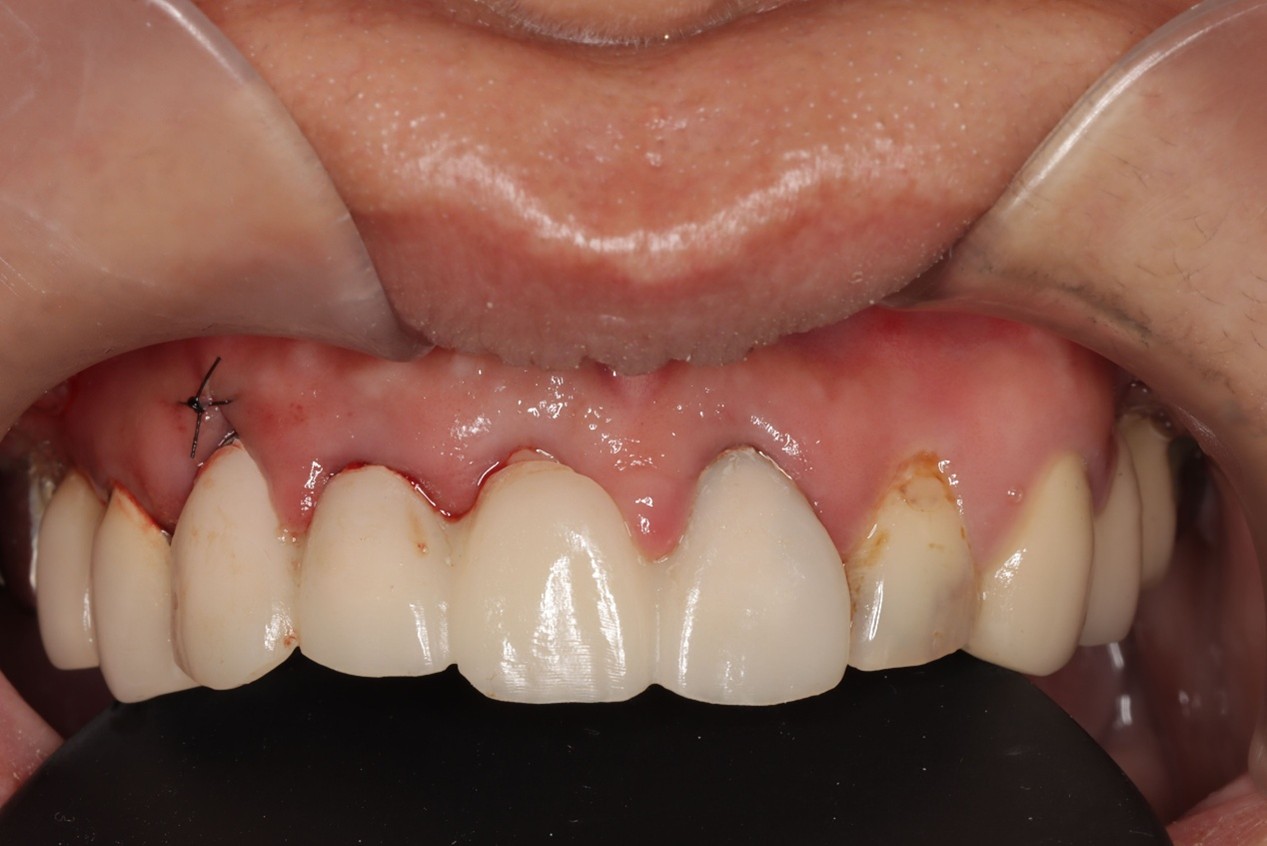

同步反應口腔位置,讓醫師能即時避開血管、神經、縮小創口,達到「真・微創植牙」,加速術後癒合,幫助患者迅速找回笑容自信,讓植牙也能成為無上體驗。

- 創口小癒合快,達到「真・微創植牙」